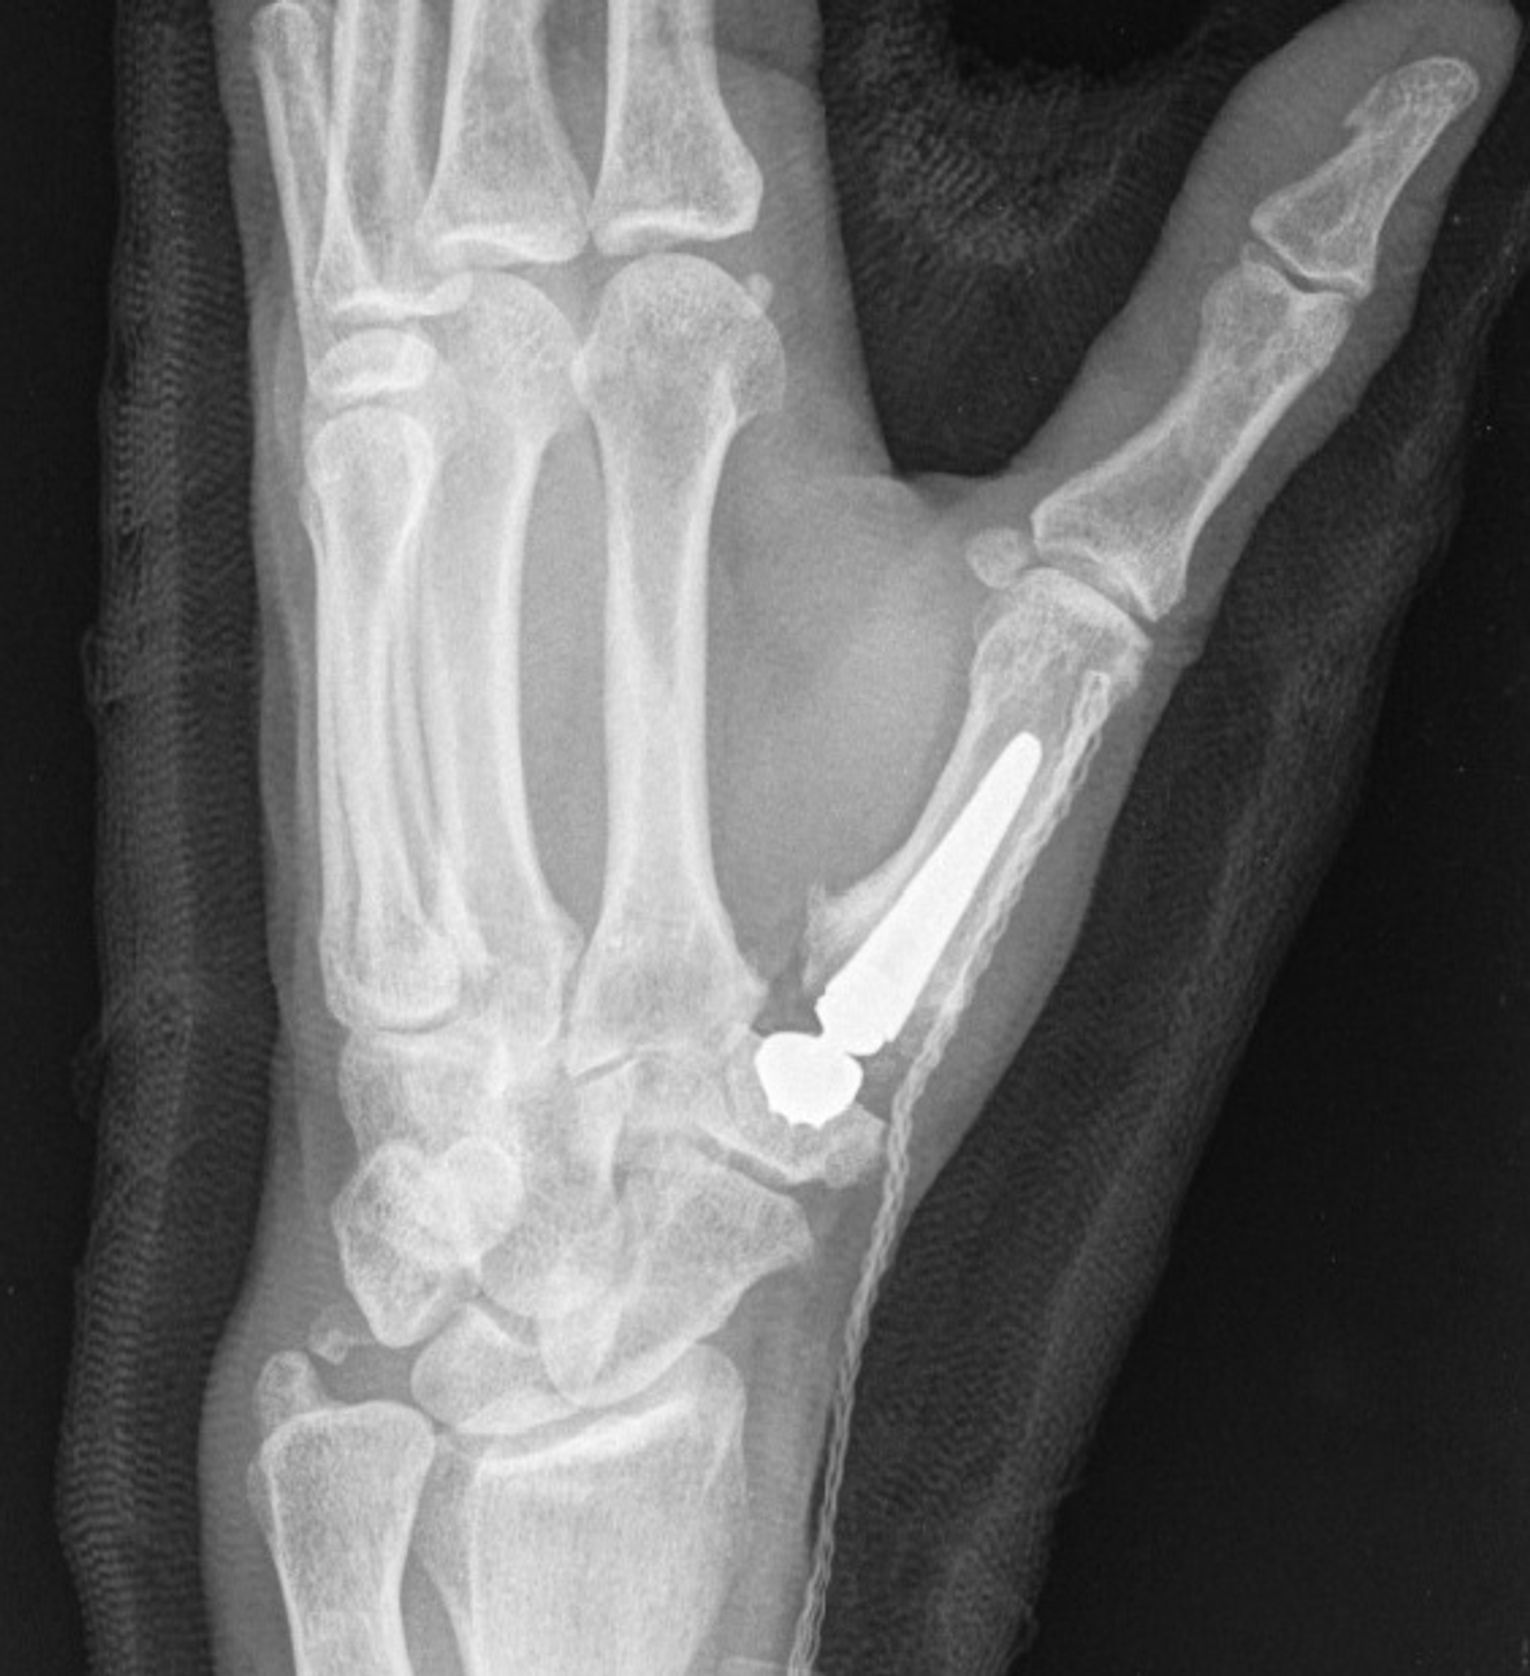

Na czym polega zabieg?

Staw zastępowany jest endoprotezą, co pozwala:

Dzięki nowoczesnej technice i implantom Touch CMC I pełna ruchomość ręki wraca już po ok. 6 tygodniach!

Proteza jest dwumobilna, co oznacza, że: zapewnia naturalny ruch w dwóch miejscach, gwarantuje pełną stabilność i minimalizuje ryzyko zwichnięcia.